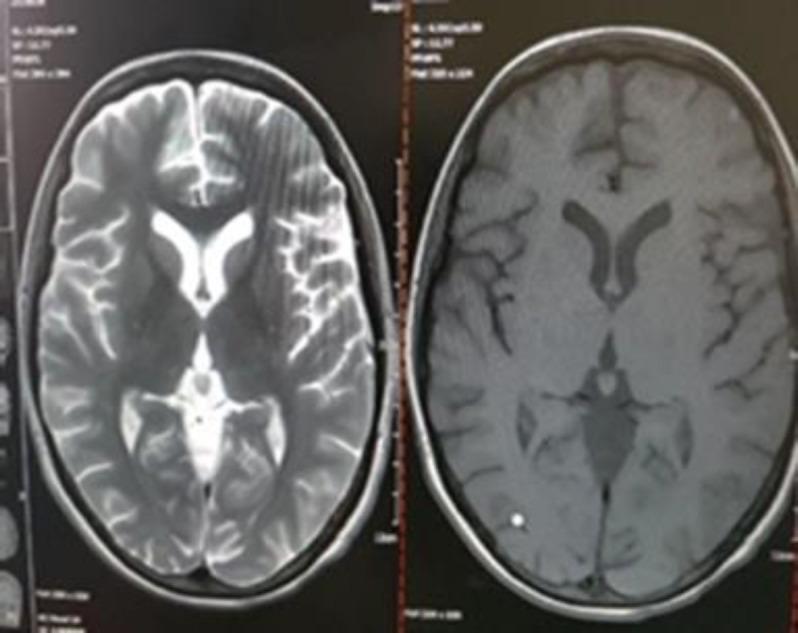

Herein, we present the case of a 35-year-old woman with diagnosis of B-cell lymphoma and rhino-orbito-cerebral mucormycosis (ROCM). She was a candidate for enucleation of the left eye, orbital decompression, and sinocerebral debridement. Nevertheless, the patient refused eye enucleation and craniotomy. Finally, she was treated with a combination of antifungals and sinus debridement without eye enucleation and craniotomy.

在此,我们报告一例35岁诊断为B细胞淋巴瘤合并鼻眶脑毛霉病(ROCM)的女性病例。她曾是左眼摘除、眼眶减压和鼻窦脑清创术的候选者。然而,患者拒绝眼球摘除和开颅手术。最后,她接受了抗真菌药物联合鼻窦清创治疗,未进行眼球摘除和开颅手术。